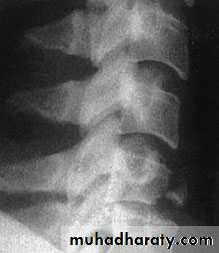

Axial compression or burst injury

Severe axial compression may ‘explode’ the vertebral body, causing failure of both the anterior and the middle columns. The posterior column is usually, but notalways, undamagedAnteroposterior x-rays may show

spreading of the vertebral body with an increase of the interpedicular distance

Posterior displacement of bone into the

spinal canal (retropulsion) is difficult to see on the plain lateral radiograph; a CT is essential.